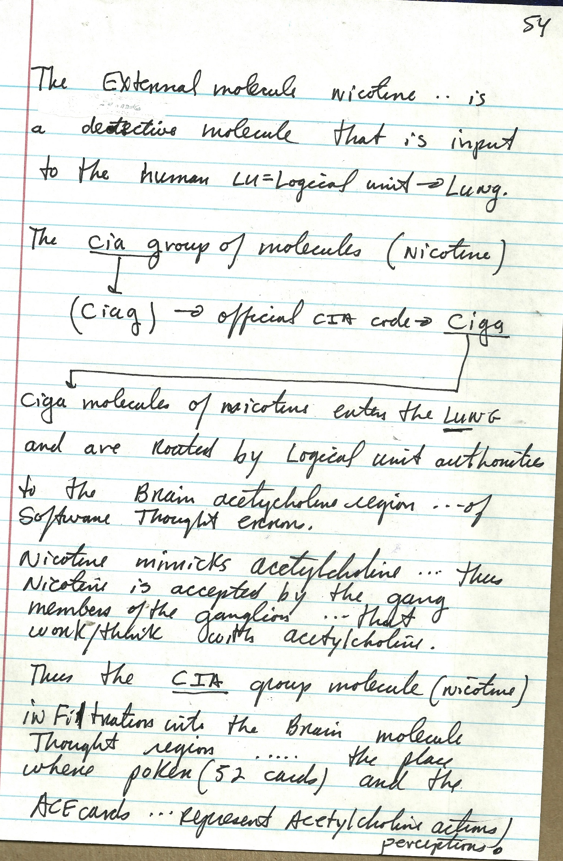

55 brain levels of thought